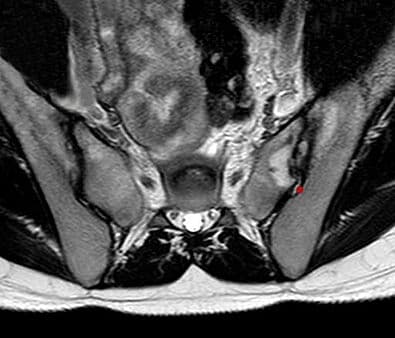

Secure your prostate health with Multiparametric Prostate MRI. Superior MRI imaging technology for early diagnosis. With the expertise of a medical imaging center.